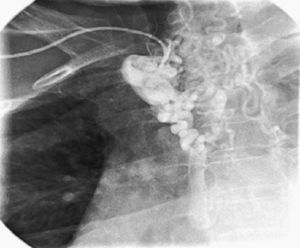

In order to exclude coronary artery disease (for surgical purposes) coronary angiography was also performed which revealed, once again, marked collateral circulation via the internal mammary artery and no coronary lesions (Figure 4). On retrospective review of the chest radiography, inferior rib notching was evident (Figure 5).